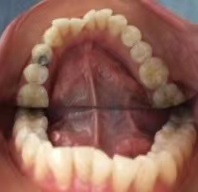

对比了一下国内和英国的隐适美价格,我发现隐适美在英国比较便宜,而且英国医生设计的方案治疗时间比较短,不需要动辄两三年。我的下牙比较拥挤(你们见过呈W形状的牙列吗…见图片),上门牙突出,又很长,还有一颗倔强有个性的门牙呈45度旋转。医生给我推荐的方案时间都控制在了一年内。